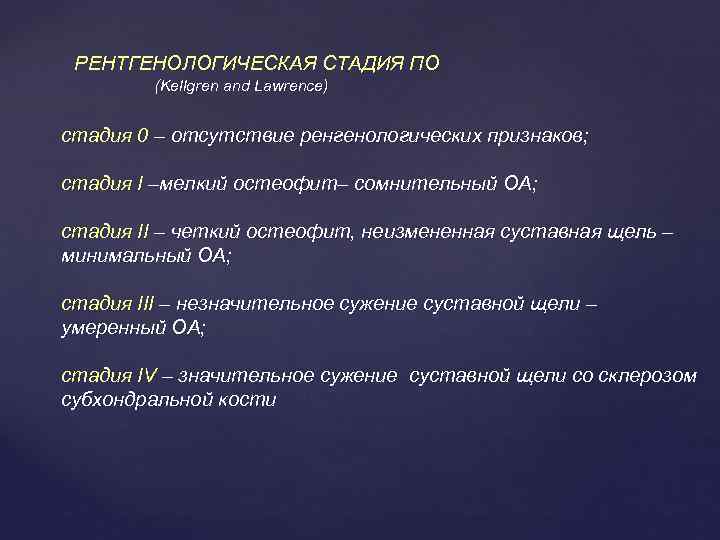

РЕНТГЕНОЛОГИЧЕСКАЯ СТАДИЯ ПО (Kellgren and Lawrence) стадия 0 – отсутствие ренгенологических признаков; стадия I –мелкий остеофит– сомнительный ОА; стадия II – четкий остеофит, неизмененная суставная щель – минимальный ОА; стадия III – незначительное сужение суставной щели – умеренный ОА; стадия IV – значительное сужение суставной щели со склерозом субхондральной кости

РЕНТГЕНОЛОГИЧЕСКАЯ СТАДИЯ ПО (Kellgren and Lawrence) стадия 0 – отсутствие ренгенологических признаков; стадия I –мелкий остеофит– сомнительный ОА; стадия II – четкий остеофит, неизмененная суставная щель – минимальный ОА; стадия III – незначительное сужение суставной щели – умеренный ОА; стадия IV – значительное сужение суставной щели со склерозом субхондральной кости